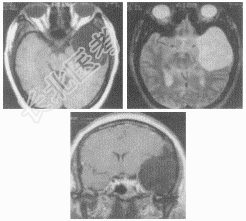

- [材料题] 女性,55岁,鼻塞、头痛1周,无任何阳性体征。

- 简答题2、患者行MRI检查图像如下:首先考虑患者的诊断及依据是什么?